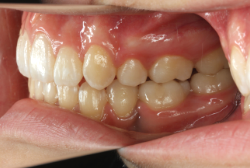

「乳歯が生え替わらない」という主訴で来院したケースです。 診断の結果、「左上永久犬歯が第一小臼歯後方上部に埋伏しているため、左上乳犬歯が晩期残存している症例」と判明しました。

このような症状の場合は、手術で埋伏している永久歯に金具を取り付け、矯正装置で牽引する必要があります。同時に凸凹の解消と前突した前歯を内側に入れるために上下左右の小臼歯を抜歯させて頂くことといたしました。

この方の場合は、マルチブラケット装置にて治療を開始し、治療期間2年3ヶ月で終了しました。犬歯の牽引距離が非常に大きかったため当院の平均治療期間よりも大幅に期間がかかりましたが、埋伏犬歯を完全に正しい位置まで誘導することができました。同時に 前歯の前突と配列の凸凹も解消しました。

このような症例は、成人してしまうと埋伏歯の反応性が悪く、あまりにも動きが悪い場合は牽引をあきらめて抜歯する場合もあります。歯科医院の検診で親知らず以外の埋伏歯を指摘された場合は、できるだけ早く矯正専門医に御相談下さい。